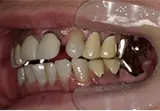

| 年齢/性別 | 60代女性 |

| 主訴 | 前歯が前に出てきた |

| 治療内容 | 全体的に歯周病やむし歯、根の治療(ヘミセクション)を実施。右上の歯にはサイナスリフト術を行い、骨の回復を待った後、半年後に2本のインプラントを埋入しました。 |

| 治療期間 | 9か月 |

| 費用 | 1,298,000円税込 |

| リスク・副作用 | 炎症反応によって術後に腫れや副鼻腔炎が生じることがあります。その程度は、手術の範囲や方法によって異なりますが、多くの場合、時間の経過とともに徐々に治まります。

ごく稀に、下顎奥歯の外科手術後に、唇や顎に痺れを感じることがあります。 |